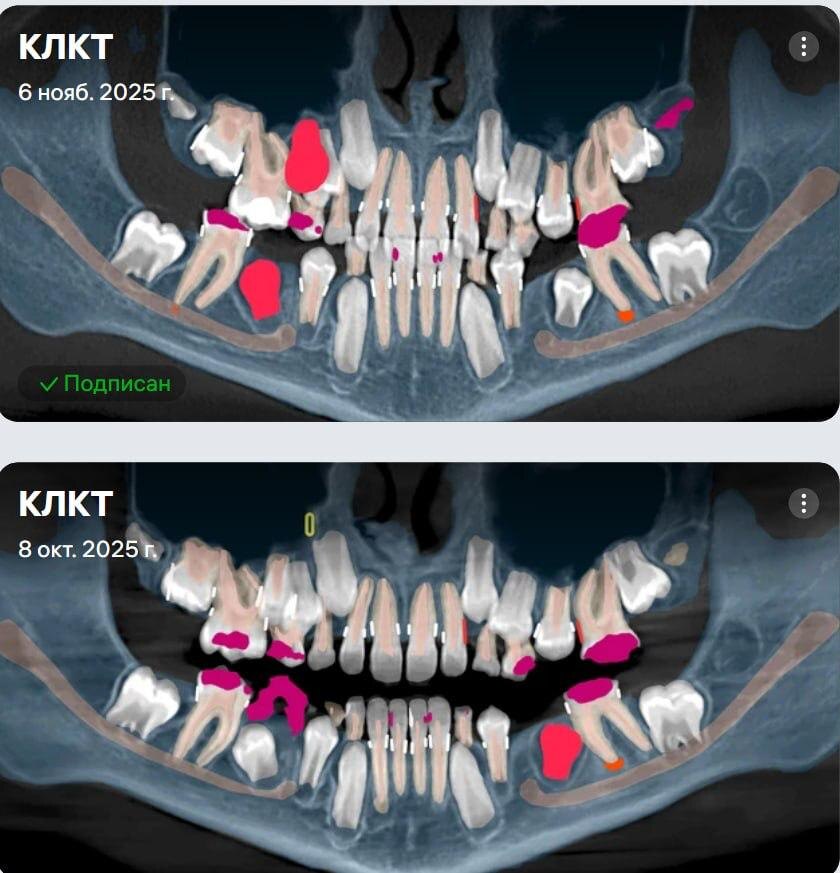

Пациент — мальчик, 10 лет, семья иногородняя. Первично они обратились к нам за онлайн-консультацией. Из анамнеза: мама рассказывала, что как только зубы прорезались, они уже были с пятнами, изменённым цветом. Постепенно ткани разрушались. Они обращались к стоматологам, где-то что-то лечили, ставили пломбы, но чаще слышали: «пока лечить не нужно». Пока в своём городе они не встретили очень грамотного доктора, который объективно определил, что ситуация сложная, и порекомендовал обратиться в нашу клинику «Дентал Фэнтези». Он же предложил формат онлайн-консультации. Когда я общалась с мамой по первому снимку от 8 октября, я уже ее предупредила, что неизвестно, насколько все будет спасаемо или нет. Потому что разрушение уже почти до уровня костной ткани. Вероятно, потребуется удлинение коронковой части и последующее покрытие коронками. Прогнозы не самые лучшие у этих зубов. Плюс ещё один трудный момент — отсутствие сотрудничества ребёнка. Мама переживала, что он просто не выдержит такие ман

Когда я общалась с мамой по первому снимку от 8 октября, я уже ее предупредила, что неизвестно, насколько все будет спасаемо или нет. Потому что разрушение уже почти до уровня костной ткани. Вероятно, потребуется удлинение коронковой части и последующее покрытие коронками. Прогнозы не самые лучшие у этих зубов. Плюс ещё один трудный момент — отсутствие сотрудничества ребёнка. Мама переживала, что он просто не выдержит такие манипуляции в сознании.

И при этом она очень трепетно рассказывала про своего доктора. Я попросила связаться с ним, потому что я понимала на том первичном звонке, что ситуация намного сложнее, чем я вижу на КТ ❗️